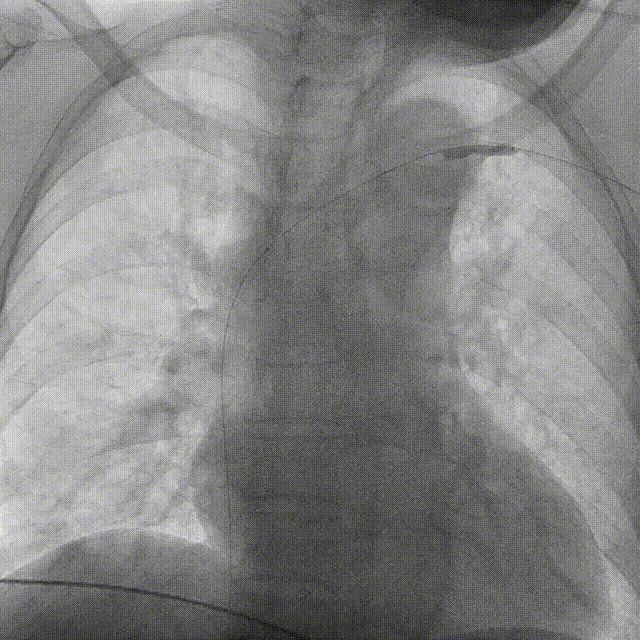

动静脉内瘘(AVF)相关狭窄/阻塞: AVF建立后,血流动力学发生剧变,高流速和湍流会增加对静脉壁的剪切力,导致内皮损伤、内膜增生和纤维化,最终引发狭窄或闭塞。

图:动静脉内瘘(AVF)相关狭窄/阻